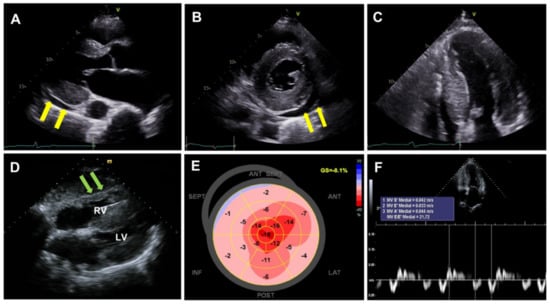

Echocardiography is an advantageous and widely applicable diagnostic technique employed for the evaluation of patients with suspected heart failure symptoms [28,33,34]. Combination of increased left ventricular wall thickness (≥12 mm) on echocardiography and low to normal QRS voltage on ECG is the hallmark of CA. It is crucial to accurately measure left ventricular wall thickness using the parasternal long-axis view. Additional CA-associated features include small left ventricular cavity volume, biatrial enlargement, thickened valves and right ventricular free wall, restrictive diastolic pattern, and a small amount of pericardial effusion (Figure 2) [2,28]. Interestingly, pericardial or pleural effusion has been documented in more than half of CA patients [35], thus acting as a distinguishing feature from hypertrophic cardiomyopathy [34]. Potential mechanisms for pericardial or pleural effusion in CA include right ventricular failure and serosal infiltration of amyloid deposits. It is known that pericardial or pleural effusion alone is not specific to CA; it can also be found in many other inflammatory cardiac diseases, particularly in cases involving the right heart. However, pericardial effusions along with other echocardiographic peculiarities warrant clinical suspicion of CA [34]. A “granular sparkling” appearance of myocardial texture has been conventionally considered as a typical echocardiographic feature [34]. However, it has been confirmed to be a nonspecific finding [36,37] as it is also frequently manifested in other conditions, such as end-stage renal disease. Moreover, the harmonic echocardiographic imaging technique could result in confounding findings [38].

Figure 2. Echocardiographic findings of cardiac amyloidosis. (AC): Thickened left ventricular wall (≥12 mm) with a granular sparkling appearance of myocardial texture and a small amount of pericardial effusion (yellow arrow), (D): right ventricular free wall hypertrophy (green arrow), (E): apical sparing of longitudinal strain (bull’s eye or cherry on top pattern), (F): deteriorated diastolic function.

A wide spectrum of diastolic dysfunctions, ranging from grade 1 impaired relaxation to grade 3 restrictive filling, can be detected by the severity of amyloid infiltration [2,28]. It has been documented that the left ventricular ejection fraction is usually preserved until the late phase of CA progression [27,39]. Despite the preserved ejection fraction, left ventricular performance is known to deteriorate from the earlier phases [39,40,41]. The early stages of CA are characterized by infiltration originating in the sub-endocardium, which mainly comprises longitudinal fibers [38]. Therefore, longitudinal indices of myocardial contraction (not the radial/circumferential ones) may serve as early markers of systolic dysfunction [38,39]. Particularly, regional longitudinal strain variation, referred to as “relative apical sparing” might be helpful in distinguishing CA from other causes of left ventricular hypertrophy [42]. In CA, a longitudinal strain typically suggests an impaired basal/mid-segmental strain but preserved apical longitudinal strain, which results in “bull’s eye or cherry on top pattern” when the segmental strain is plotted (Figure 2). Several metrics have been suggested to objectively quantify the degree of relative apical sparing. Phelan et al. proposed the relative apical sparing index as follows: average apical longitudinal strain/average basal and mid-longitudinal strain. In their study, the ratio of 1.0 showed appropriate sensitivity and specificity in differentiating CA from other causes of hypertrophy (hypertrophic cardiomyopathy and aortic stenosis) [42]. Liu et al. calculated the septal apical longitudinal strain/septal basal longitudinal strain, and the cutoff value of >2.1 showed an optimum diagnostic performance in differentiating other etiologies of hypertrophy [43]. The suggested mechanisms include (1) less amyloid deposition at the apex than at the base, (2) greater diversity of myocyte and matric orientation at the apex as compared with the base, and (3) greater tendency toward apoptosis and remodeling in the basal segment related to turbulent flow in the left ventricular outflow tract and higher parietal stress [44,45].